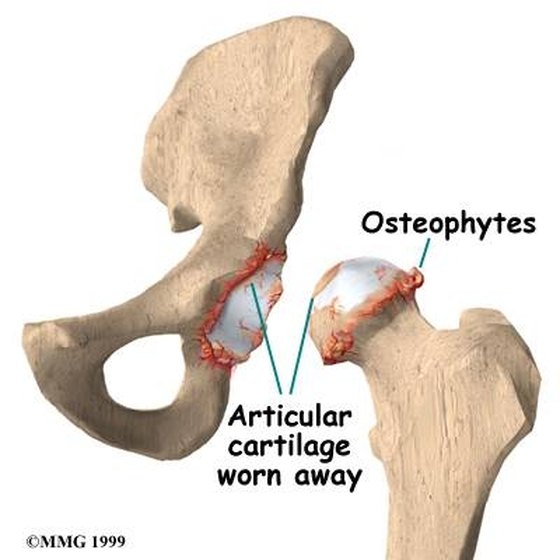

Arthritis (Spine) And Bone Spurs